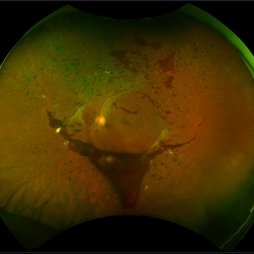

Closed Funnel Retinal Detachment

Ultra-wide field pseudocolor image of a 57-year-old male with a closed funnel retinal detachment with anterior and posterior napkin rings affecting his left eye. Patient presented with klebsiella endophthalmitis in UK, and was in medically induced coma with tracheostomy. He awoke after sedation with loss of vision in both eyes, later developing a retinal detachment in both eyes. Prior inflammation attributable to prephthisical state and chronic funnel retinal detachment. The eye is inoperable and observation is recommended.

Photographer: Olivia Rainey and Amber Poss

Imaging device: Optos

Condition/keywords: blind eye, funnel, hypotony, klebsiella endopthalmitis, left eye, Optos